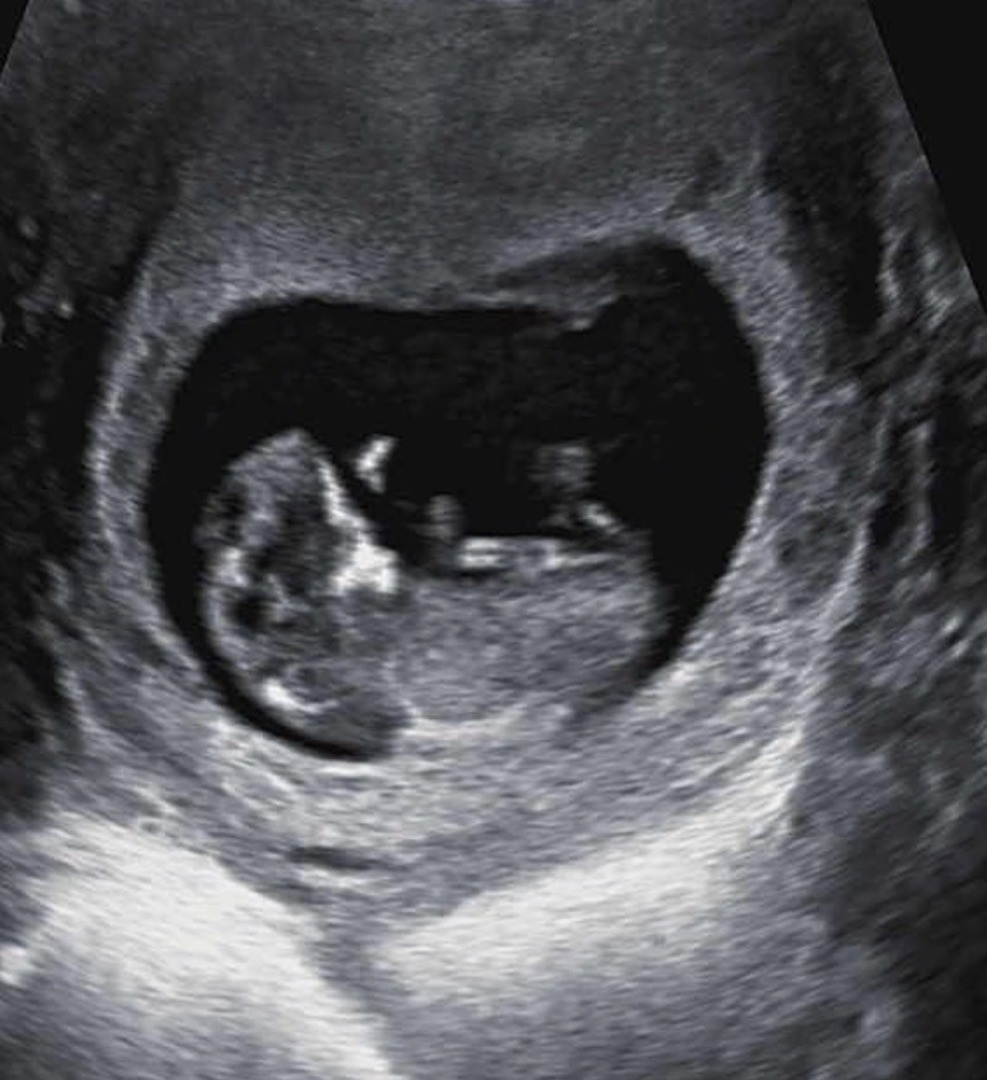

니프티 결고ㅏ 아들이었습니다~~^^

각도법 참견해주세요~~~

각도법 마구마구 참견해주세요~~🩷